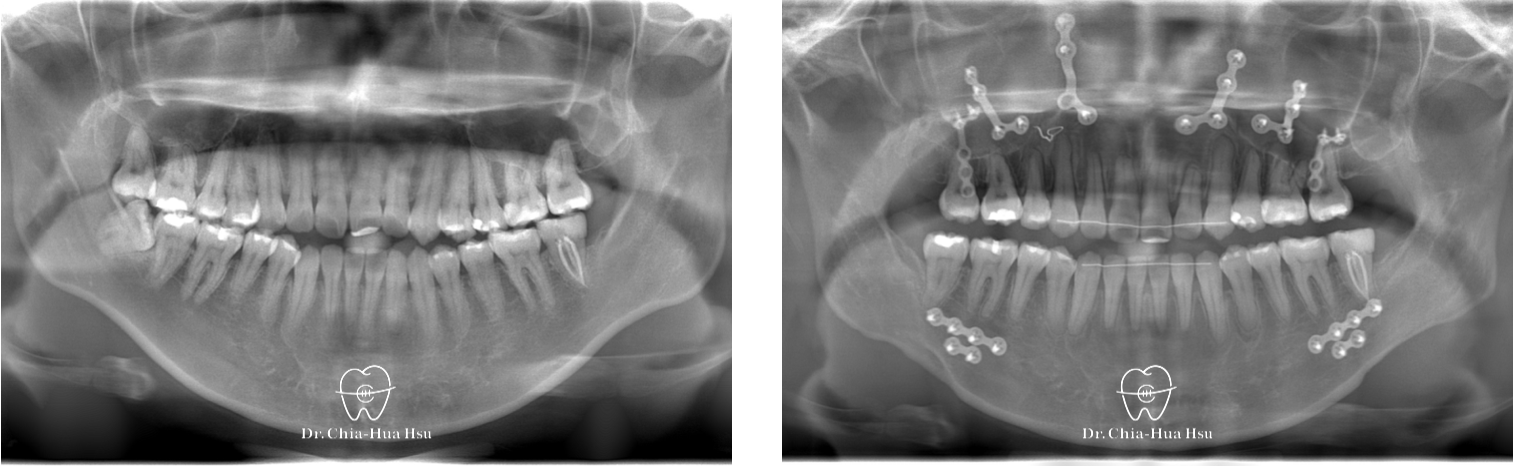

戽斗、前牙錯咬、開咬

成⼈矯正 | ⾦屬矯正 | 正顎⼿術

治療前

治療後